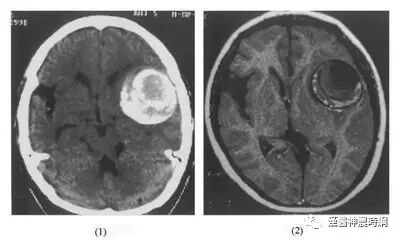

1.颅内肿瘤 鞍上区动脉瘤常误诊为鞍区肿瘤,但鞍上区动脉瘤没有蝶鞍的球形扩大,缺乏垂体功能低下的表现,颅内肿瘤卒中出血多见于各种胶质瘤,转移瘤,脑膜瘤,垂体瘤,脉络丛乳头状瘤等,在出血前多有颅内压增高及病灶定位体征,无再出血现象,据CT扫描及脑血管造影可容易鉴别。